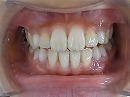

治療前 治療後

今回の症例は上下の前歯の位置関係が改善していますが、

顎骨の劣成長等の関係で

全ての症例で必ずしも前歯の位置関係が良好な状態となる訳ではありません。

また今後、2次・3次的な治療が必要となる可能性があります。